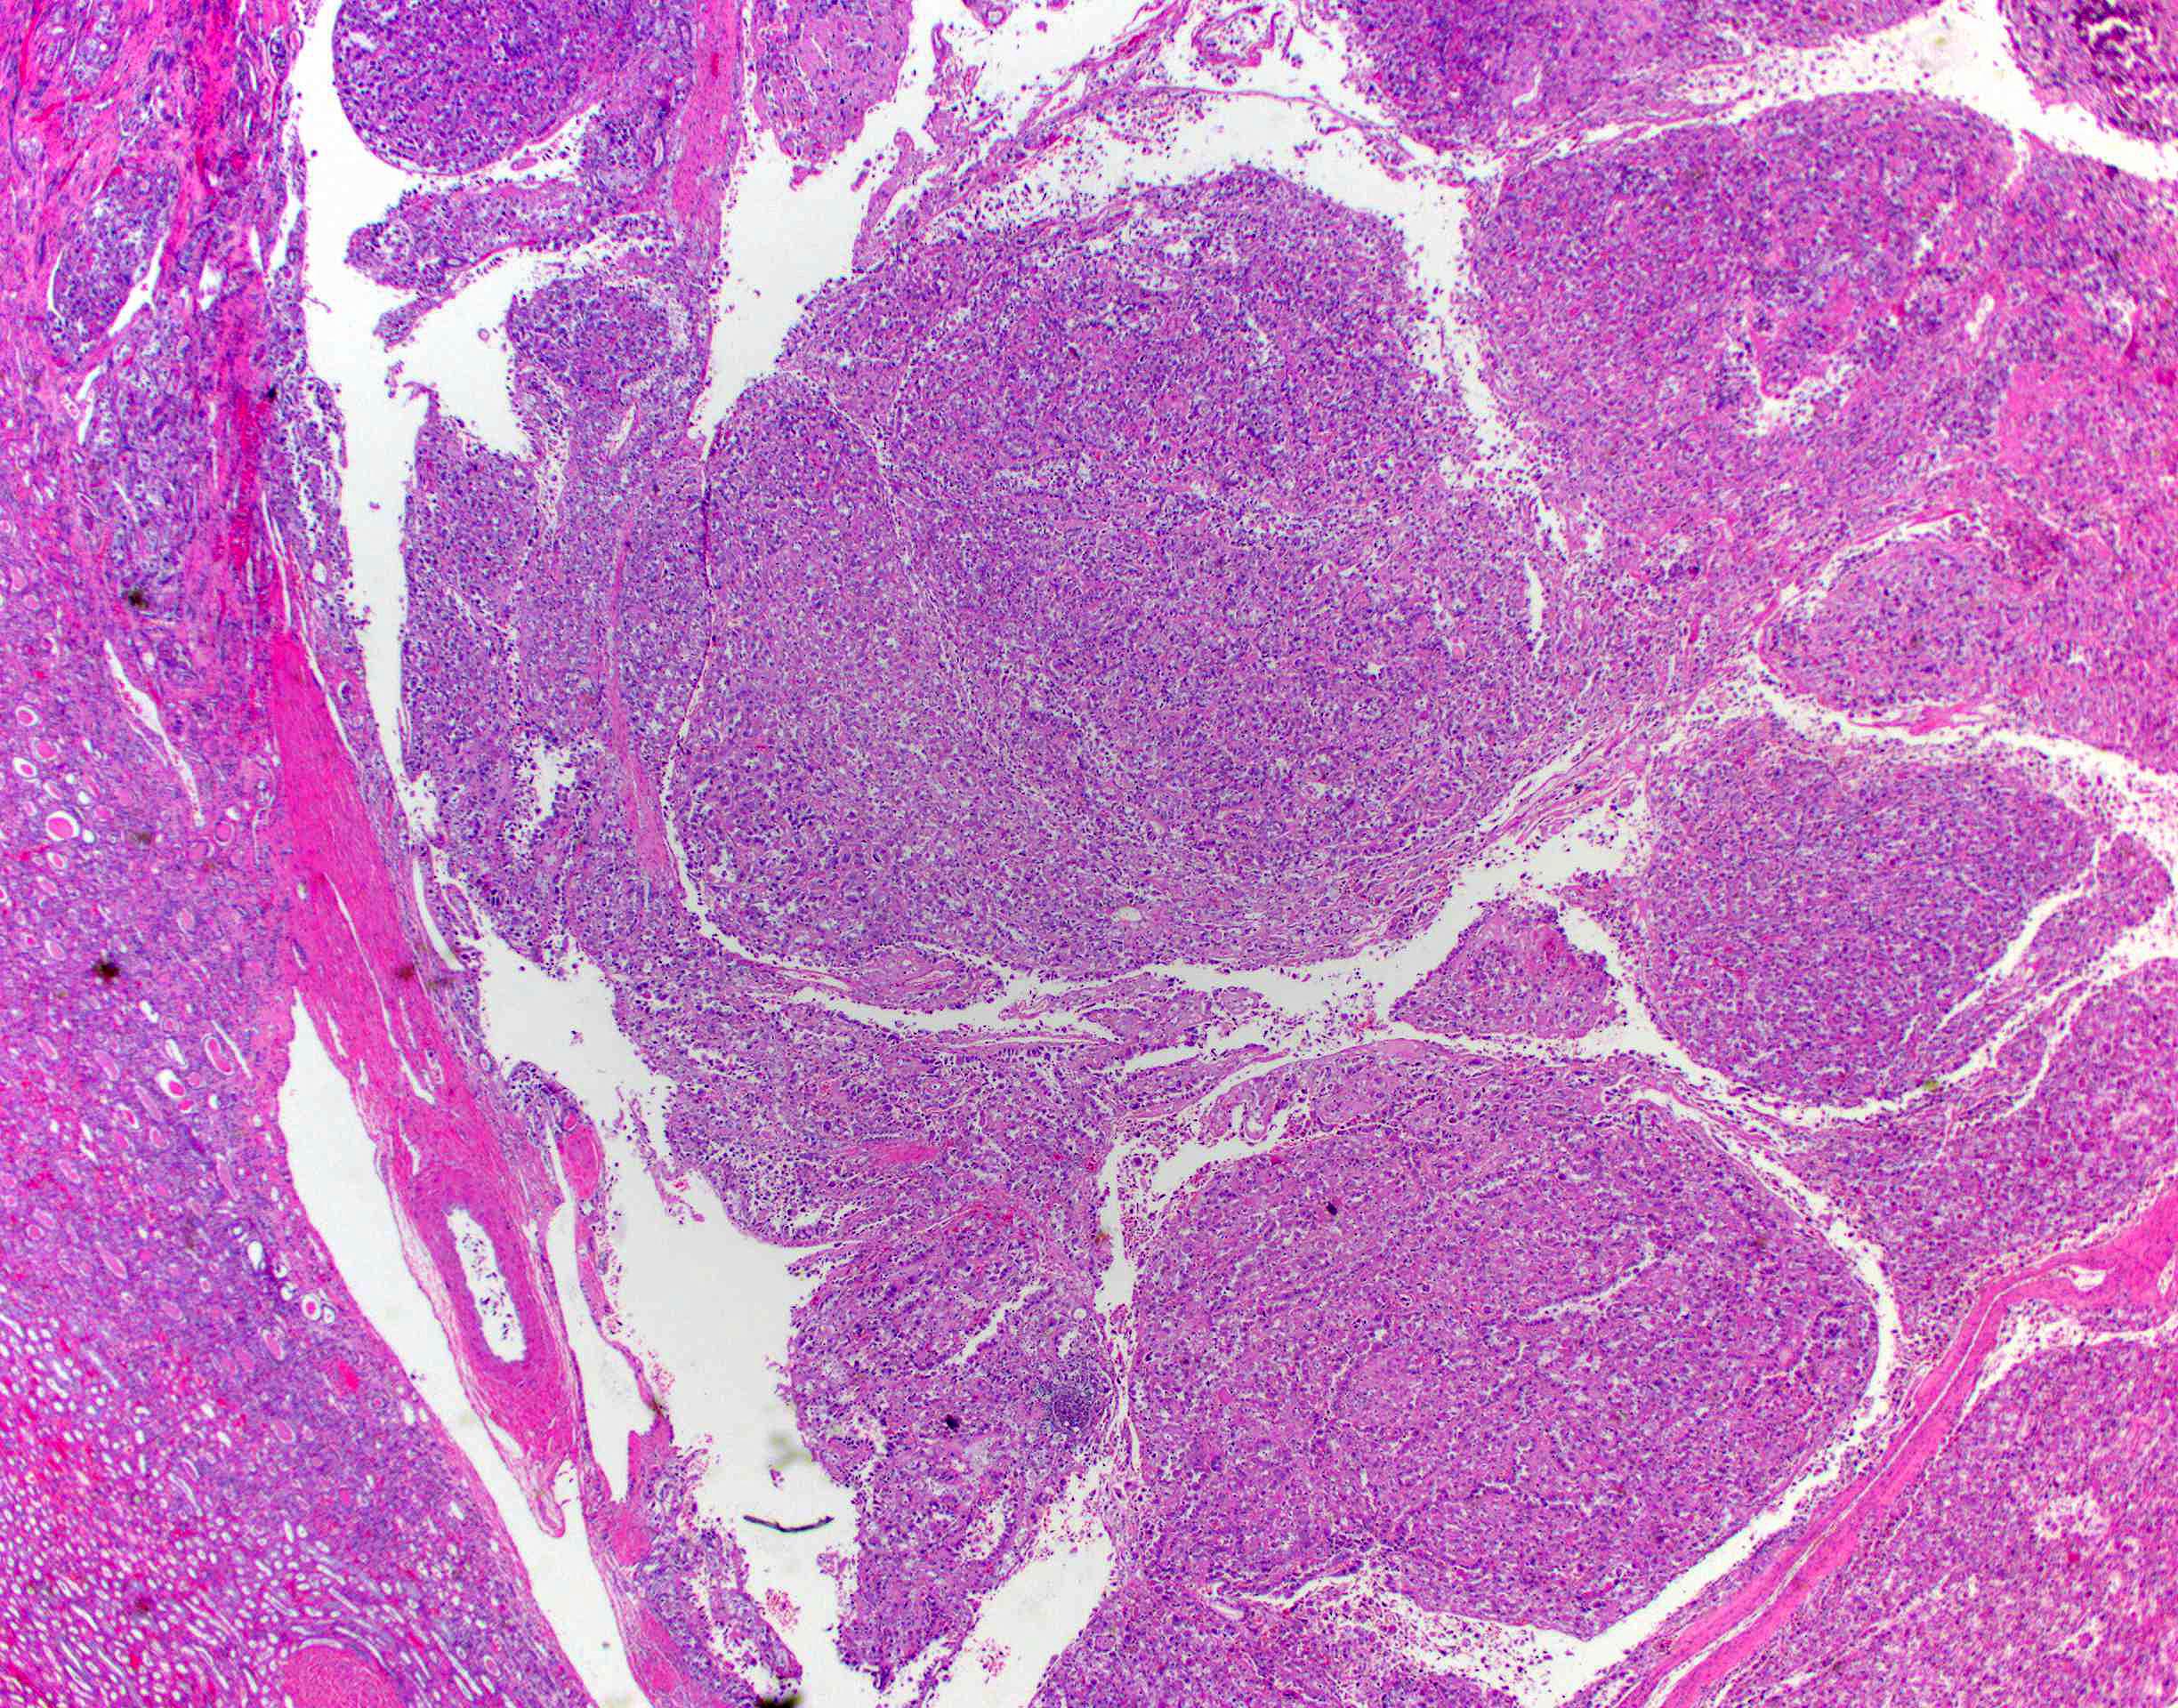

Renal tumor grading

Case ID: 419